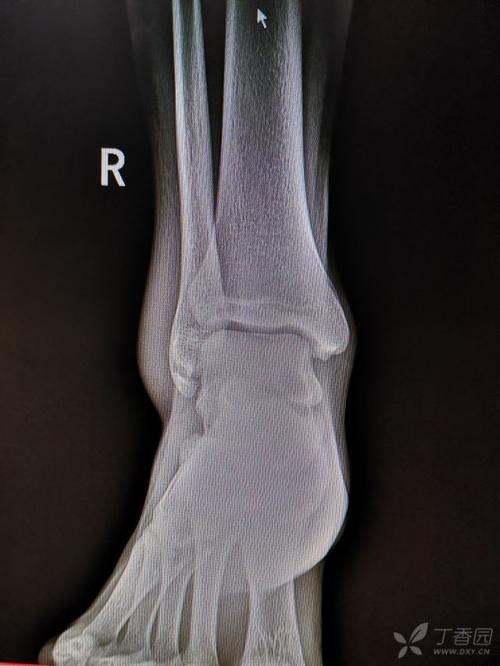

患者,男,17岁,扭伤致右踝关节肿痛活动受限3天.dr及ct如下

脚扭伤了做ct影像表现是,左踝关节在位,关节间隙尚可